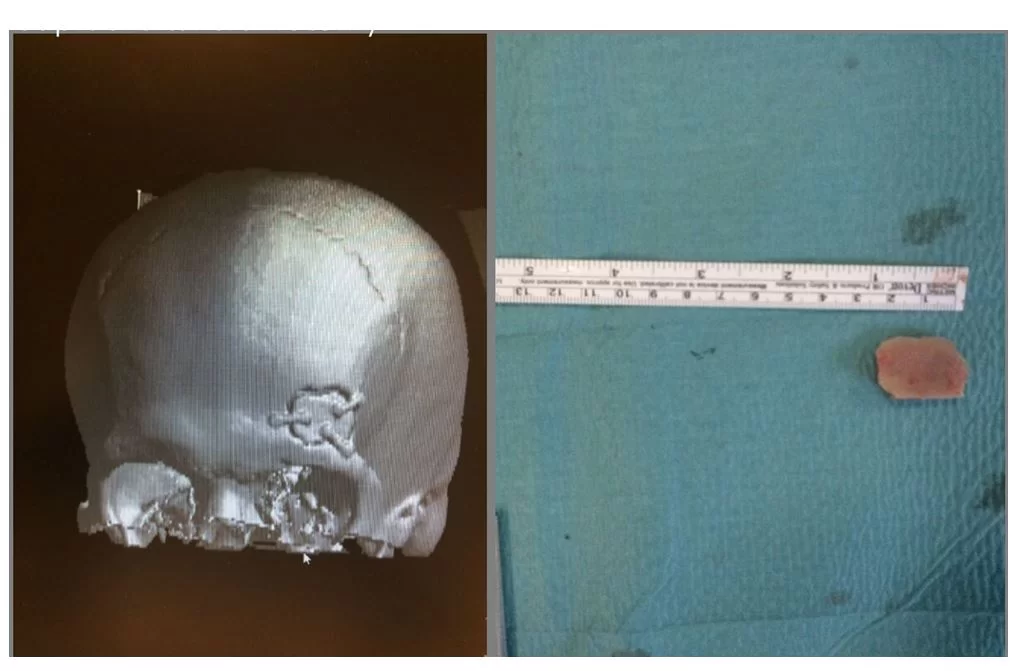

Ένα επίσης σημαντικό πλεονέκτημα της μεθόδου είναι το άριστο αισθητικό αποτέλεσμα (Εικόνα 1 & 2).

Μίνι οπισθομαστοειδική κρανιοτομία

Η μίνι οπισθομαστοειδική κρανιοτομία χρησιμοποιεί ένα μικρό άνοιγμα στο οστό πίσω από το αυτί (Εικόνα 3) για να προσπελάσει ακουστικά νευρινώματα, μηνιγγιώματα, επιδερμοειδείς όγκους και όγκους της παρεγκεφαλίδας όπως αιμαγγειοβλαστώματα και μεταστατικούς όγκους.